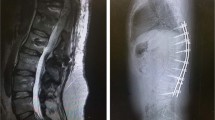

Among I6 married male paraplegic patients, eight had spontaneous erections and three ejaculations. Rectal electroejaculation gave poor results. Although hormonal and sperm metabolic values were normal, sperm analysis showed severe disturbances.

David, A., Ohry, A. & Rozin, R. Spinal cord injuries: male infertility aspects. Spinal Cord 15, 11–14 (1977). https://doi.org/10.1038/sc.1977.3